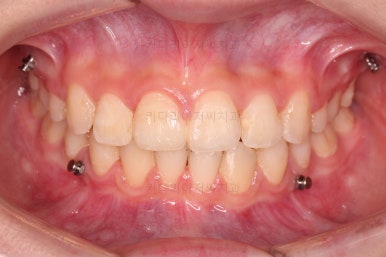

교합이 잘 맞아졌고요.

위아래 앞니도 서로 가까워졌어요.

치열도 가지런해졌고, 과개교합도 잘 개선이 되었습니다.

연산동치아교정 이제 전후 사진을 비교해 볼게요.

아래 앞니가 2개인 것이 표시가 안날 정도로 자연스럽게 교합이 맞아졌습니다.